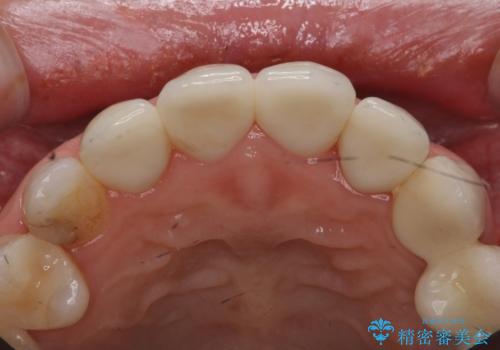

また、色を決める前にホワイトニングを行い、全体的に歯を白くしてから色を決めました。

色や形については納得いくまで修正し、最後は満足されていました。